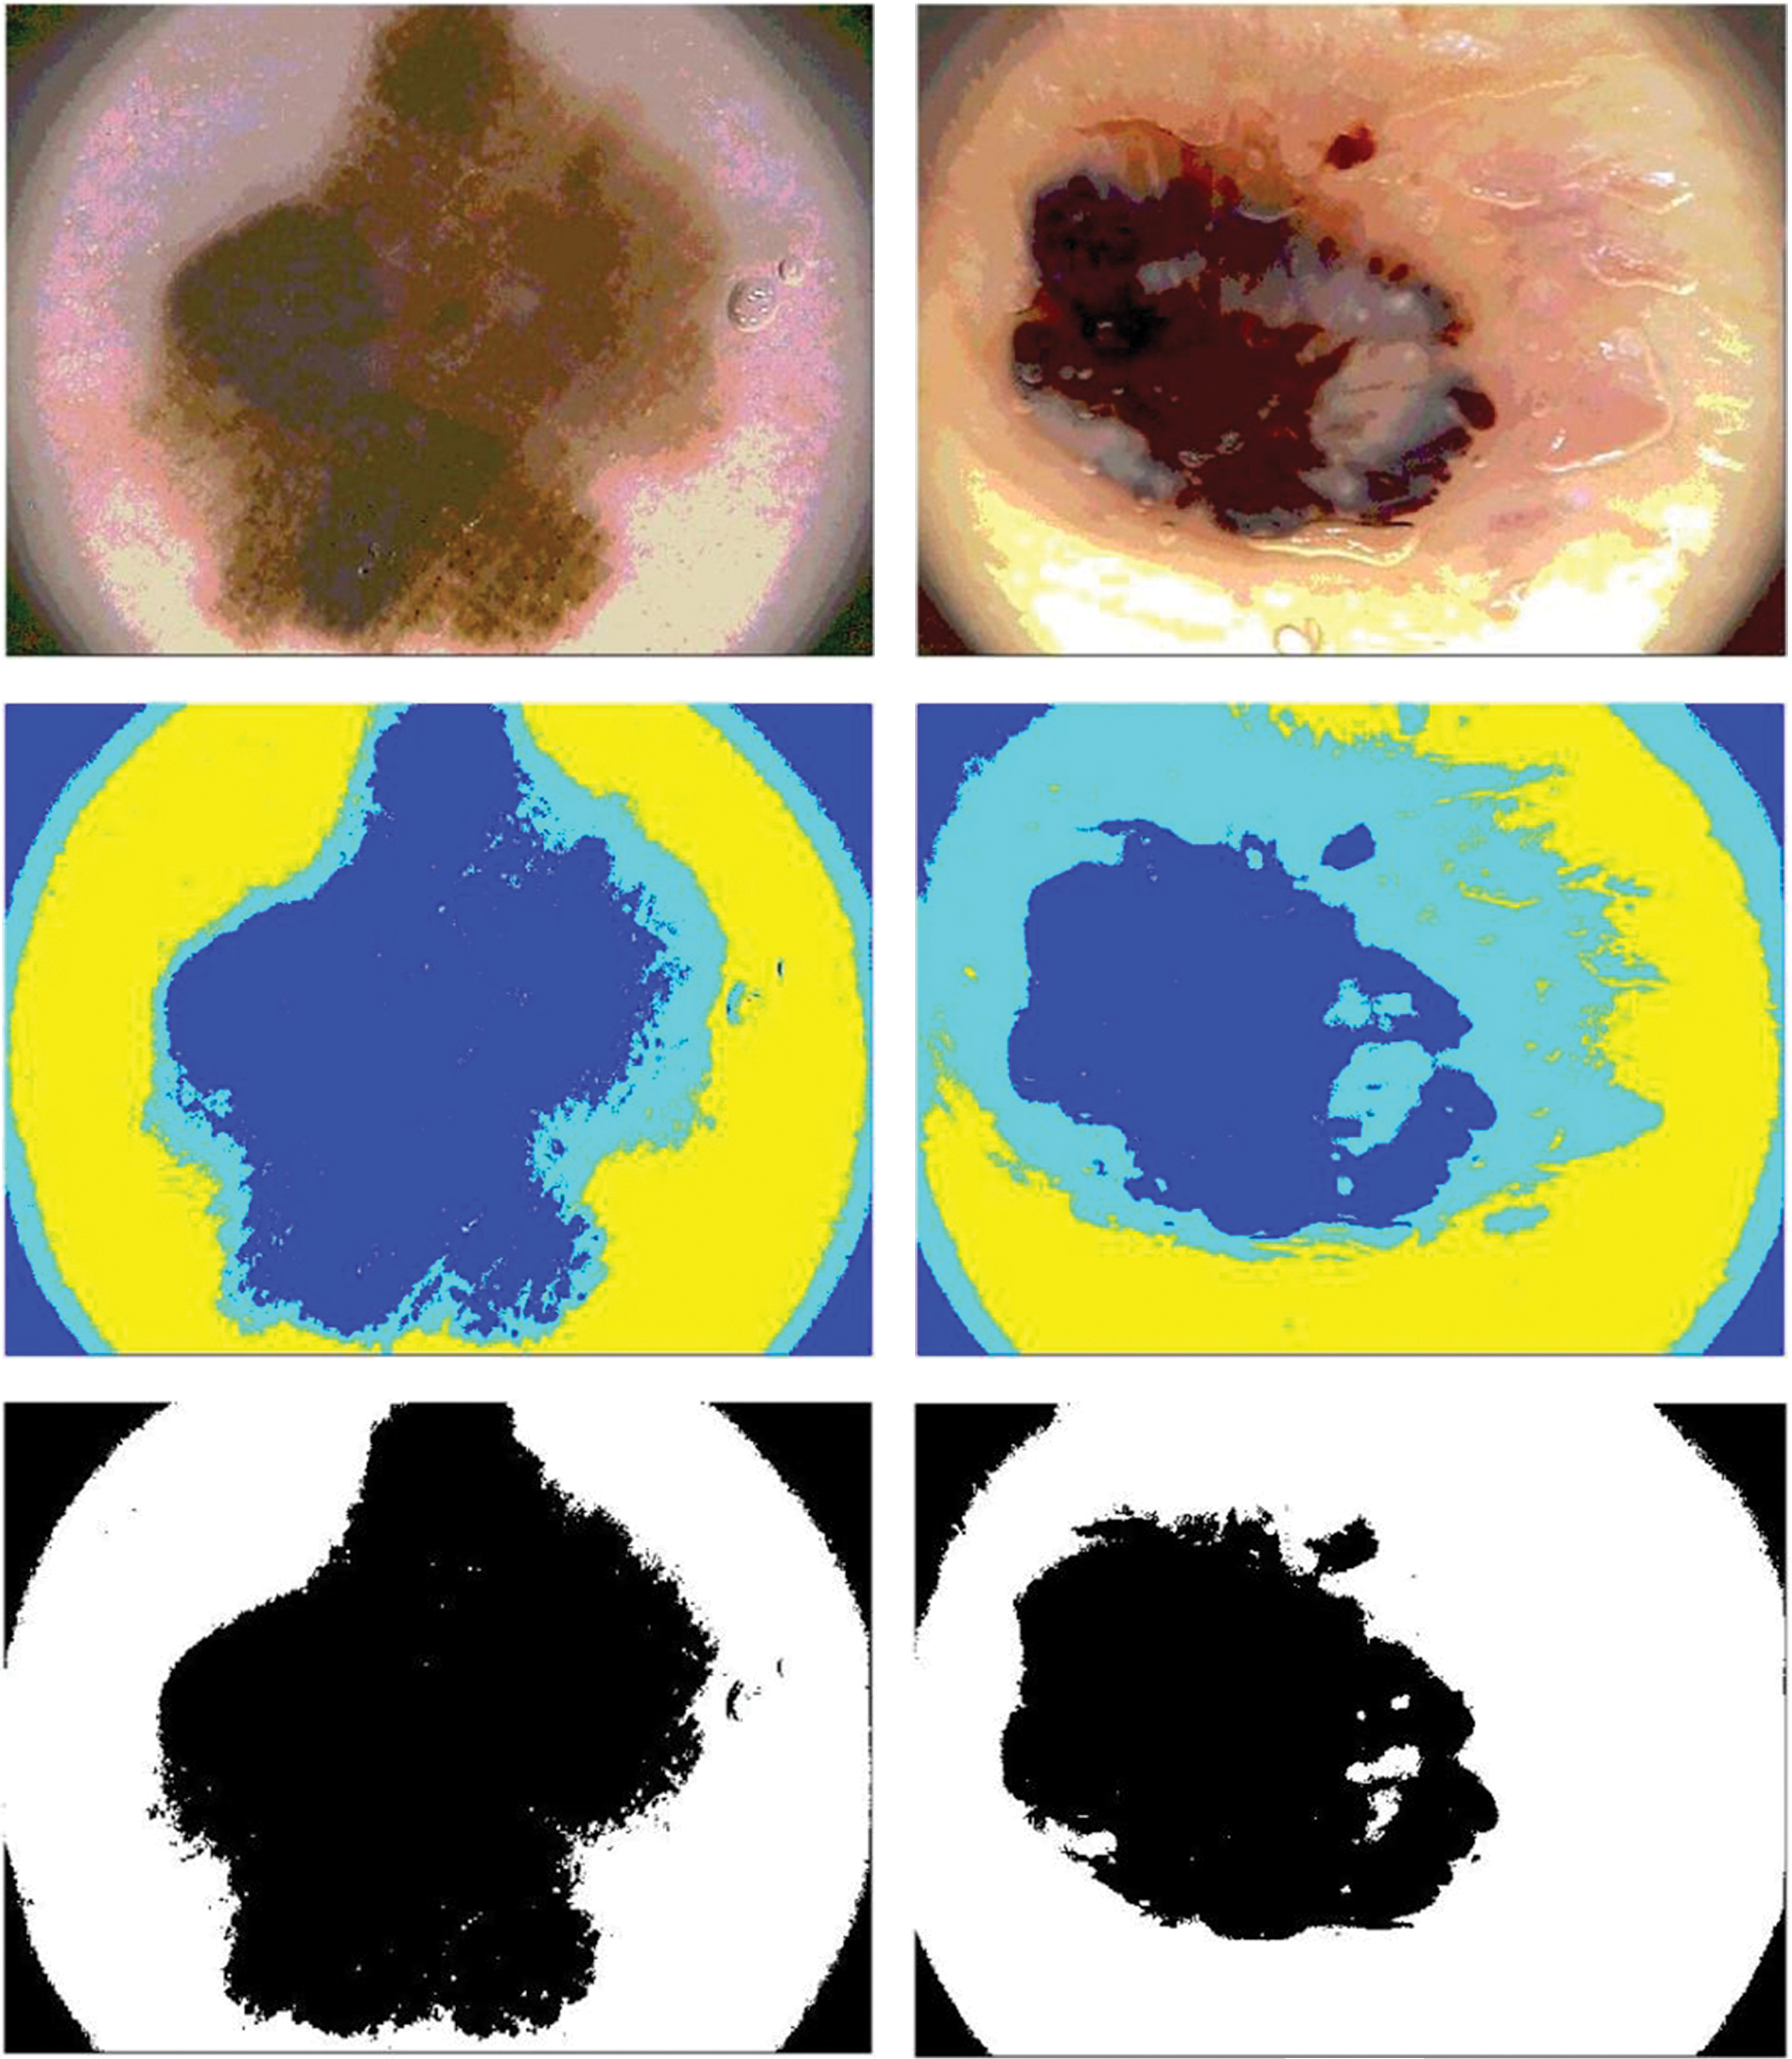

Dermoscopy was created to enhance the skin cancer diagnostic process. It is a non-invasive visualization technique that generates a brighter, more intense illustration of a specific area of skin, making skin markings easier to see. The removal of the reflecting skin surface improves the visibility of deeper skin layers and gives additional details about the lesion. Dermoscopy evaluation is a usual way of recognizing melanoma as it is more reliable than visual inspection [16]. Dermoscopic evaluation of images by specialists typically takes a significant amount of time and may result in a range of diagnostic results. As a result, automated identification methods are highly recommended. But for the reasons listed below, it is not a simple task: First, it might be difficult to differentiate between non-melanomas and melanomas owing to the similarities of benign and malignant lesions. Second, the automated identification process is more difficult due to low contrasts and unclear borders between the lesion and normal skin areas. Last but not least, the development of artifacts like hairs or air bubbles may mask the lesions. The difficulties are shown in Fig. 2. The types, causes and diagnosis approaches for skin cancer are shown in Fig. 3.

Figure 2: The process of automatically identifying melanoma from dermoscopy images is quite difficult. From top to bottom, the primary difficulties are: a significant level of visual resemblance amongst lesions that are melanoma compared to ones that are not; comparatively little difference among lesions and areas of healthy skin; and picture artifacts. Images in the left column display non-melanomas, whereas those in the right column display melanomas